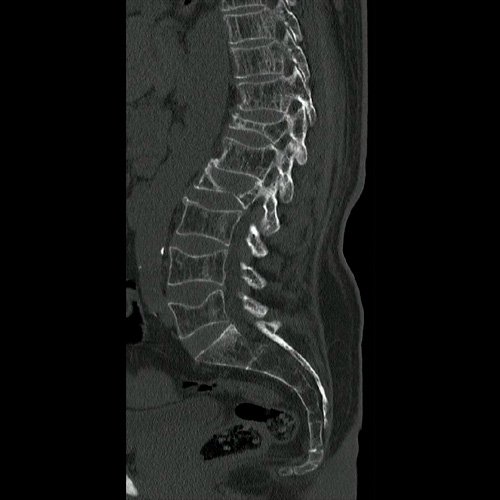

- Tomografía de columna lumbosacra (Día 0): Contamos con TC previa del día 04-09-2025 y RMI del día 28-08-2025. Hiperlordosis lumbar. Eje lumbar se encuentra desviado hacia la derecha. Persiste, de mayor jerarquía que en TC previa, la reducción de altura de los cuerpos vertebrales de D12, L2, mayor al 50%, con afectación del muro posterior. También se observa reducción del 30 % del cuerpo vertebral L4 y L5. Hallazgos en relación a fracturas aplastamiento patológicas. Además se observa marcada osteopenia generalizada. Disminución de la altura intervertebral de L2-L3 y L3-L4, a nivel de su margen posterior. Los demás espacios discales visualizados son de altura conservada. No se observan signos de protrusiones ni hernias discales. Ligera rarefacción del TCS paravertebral.

- Tomografía de abdomen y pelvis con contraste e.v. (04/09/2025): El hígado es de forma, tamaño y situación habituales. Su superficie es lisa, y sus bordes son agudos. En segmento VI se observa una lesión hipodensa, de aspecto quístico que mide 7mm. Formaciones quísticas corticales en ambos riñones, la de mayor tamaño se encuentra en polo inferior del riñón izquierdo y mide 10 mm. Calcificaciones parietales aortoiliacas. Aisladas formaciones diverticulares en colon descendente, sin complicaciones agudas. Se observa disminución de la altura de los cuerpos vertebrales de L2, L4 y L5, siendo el primer nivel mencionado el de mayor afectación superando el 50% de la altura su soma, en probable relación a fractura aplastamiento. Osteopenia generalizada con alteración del patrón trabecular normal.

- Resonancia magnética de columna lumbar (28/08/2025): fractura aplastamiento de L2, a expensas de su platillo superior, que compromete el 60% de su altura. Fractura aplastamiento de L4 y L5, a expensas de platillos superiores, que afecta menos del 30% de la altura del cuerpo vertebral, sin desplazamiento. Estos cuerpos vertebrales presentan impronta de Schmorl en la placa terminal superior y resultan hiperintensos en STIR, hipointenso en T1, hallazgo compatible con edema óseo.